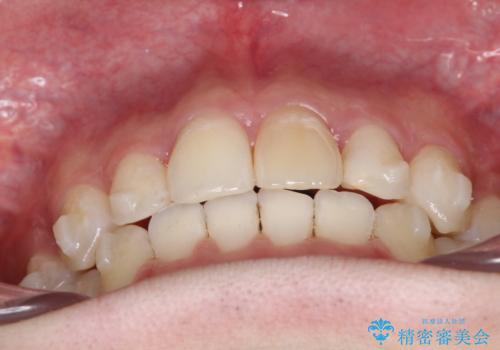

- 前歯が出ていることを主訴に来院されました。

臼歯関係が上顎前突傾向のため、上顎小臼歯を抜歯してインビザラインにて治療を行いました。

臼歯の咬合を作るために治療終盤ではゴムかけを行なっています。